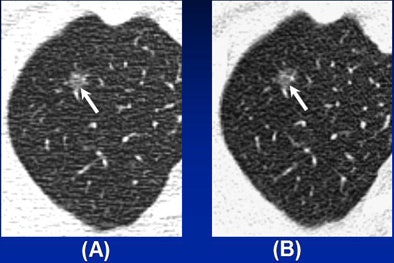

At follow-up CT at a mean of 55 months (range, seven to 73 months), GGOs disappeared in 11 subjects. Another 25 subjects were lost to follow-up, leaving 34 patients (17 men, 17 women; mean age 50) with 37 nodules that persisted more than six months or were surgically removed. Lesion size at presentation ranged from 4 mm to 15 mm (mean 8.5 mm).

"Most were 5 mm to 10 mm in size," Kim said. "Twenty-seven (54%) nodules were round, 23 (46%) nonround, and the mean density was -631 HU. Over the follow-up period, 18 nodules in 10 patients changed, most increased in size and density or density alone, she said. "Among these nodules, only one GGO was resected and proved to be adenocarcinoma," she said. That resection was performed after 34-month follow-up showed growth. Two other patients had bronchoalveolar cell carcinomas.

Patients' CEA levels ranged from 0.5 ng/mL to 4.5 ng/ml (average, 2.42 ng/mL). "Older age, larger size, nonround shape, and (multiple GGOs) are independent predictors of malignancy in ground-glass nodules," Kim said. However, most pure GGO nodules never changed in size over the 55-month follow-up. Cavitary changes were also seen in changed nodules.